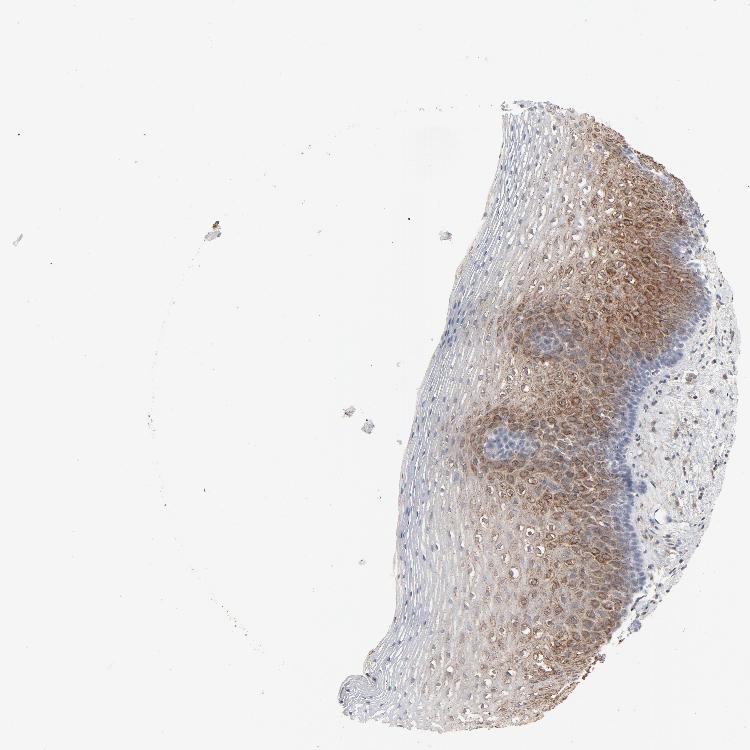

ESOPHAGUS - Antibody stainingi

Antibody staining in the annotated cell types in the current human tissue is reported as not detected, low, medium, or high, based on conventional immunohistochemistry profiling in selected tissues. This score is based on the combination of the staining intensity and fraction of stained cells.

Each image is clickable and will lead to virtual microscopy that enables deeper exploration of all samples and also displays staining intensity scores, fraction scores and subcellular localization as well as patient and tissue information for each sample.

Antibody HPA003417

Squamous epithelial cells Medium